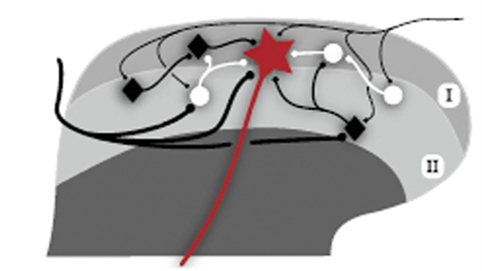

Vad är det viktiga att förstå gällande bilden?

Att de flesta A-delta-fibrer och C-fibrer terminerar i lamina 1-2

Var finns projektionsneuronen? Av vilken typ är resterande neuron här?